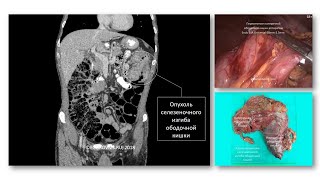

Меланома. Дерматолог и онколог: вопросы преемственности. Взгляд хирурга-онколога:

Меланома. Дерматолог и онколог: вопросы преемственности. Взгляд дерматолога